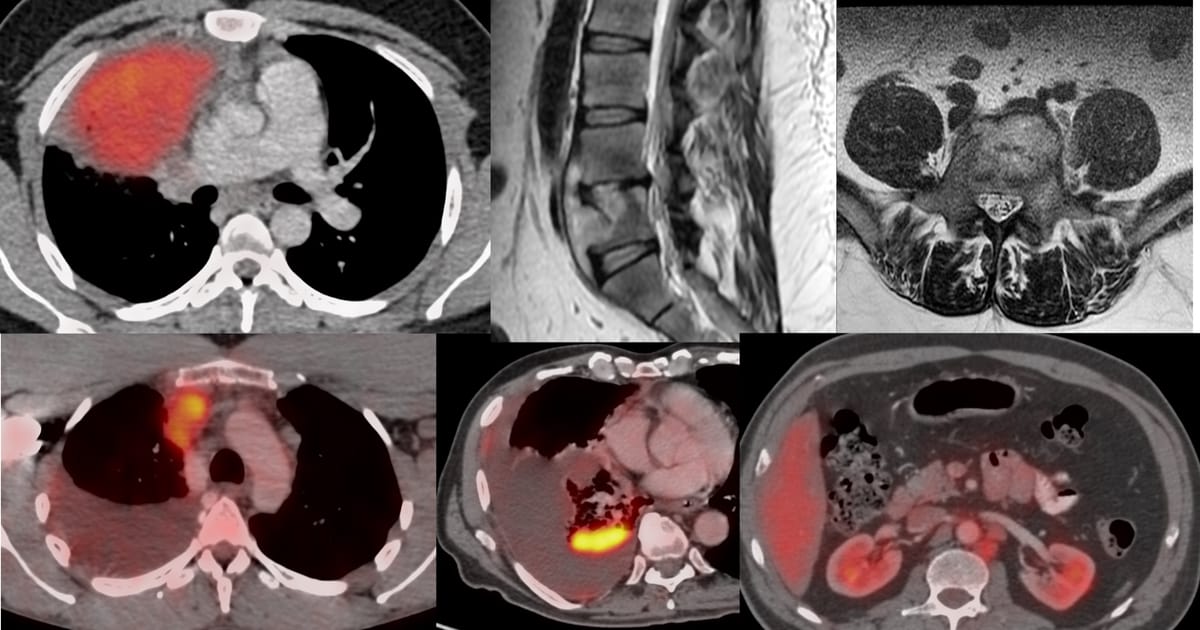

43-years old treated buccal ca had progressive lung and nodal lesions (arrow in to panel), stable liver lesions and a new S1 osteolytic lesion on PET (arrow in bottom panel) (Fig. 1).